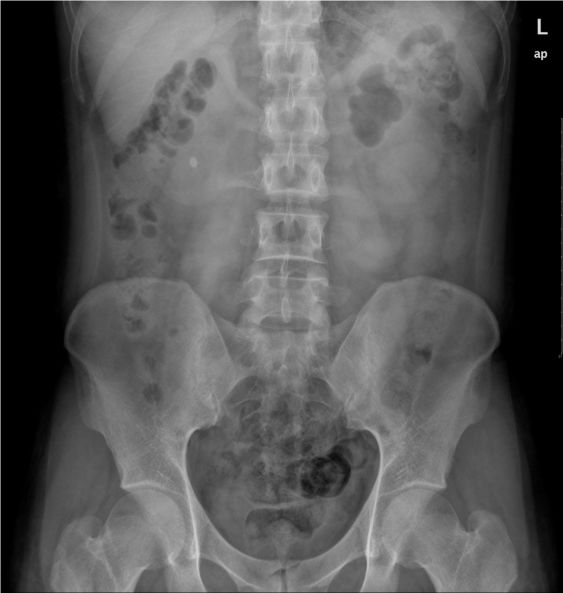

腹部平片怎么拍,腹部图片位置图

入院后行立位腹平片检查,提示腹腔可见气液平,于是对症治疗.

右肾结石:腹部卧位平片可见右侧肾区结节状高密度影.

如何看腹部平片

急诊腹部平片肠扭转大肠梗阻中毒性巨结肠腹膜后积气

腹部站立位平片讨论